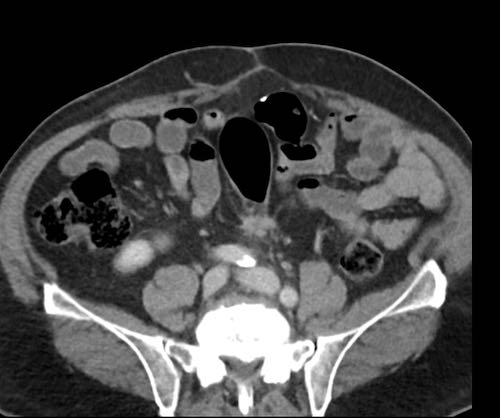

Cuộn xem ảnh CT

Ca lâm sàng 1

Cuộn qua các lát cắt.

Bạn có thể phát hiện tất cả các tổn thương cấy ghép phúc mạc không?

Bệnh nhân này đã được phẫu thuật và toàn bộ phúc mạc được ghi nhận phủ kín bởi các tổn thương u dạng kê.